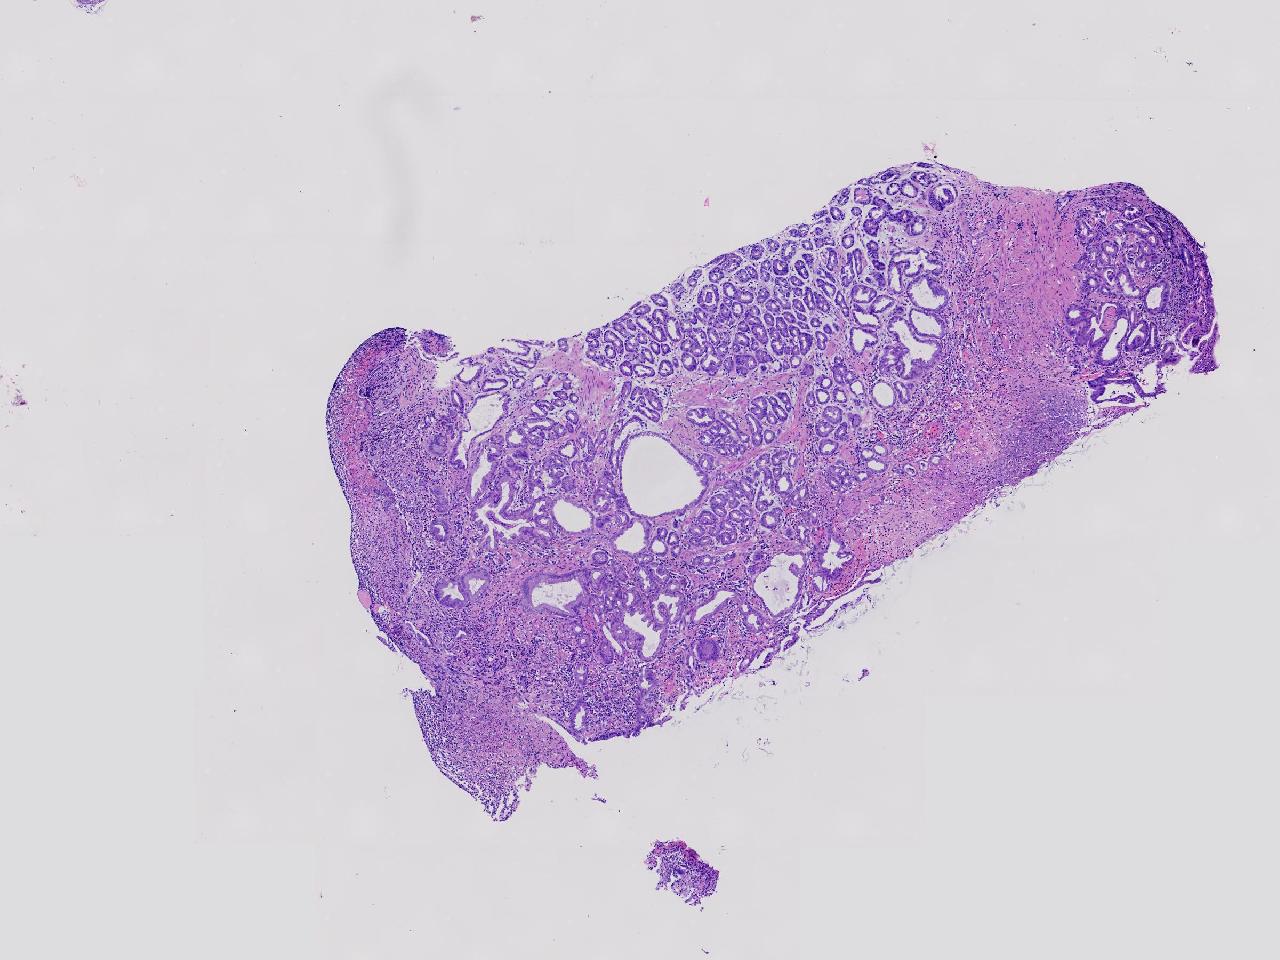

炎? 低瘤变?

胃体上部见一大小约2厘米的溃疡灶,表覆白苔,周边充血,水肿明显,活检3块。

胃体活检

灰白色不整形软组织3块,直径均0.2厘米。

深在性囊性胃炎,少量溃疡组织

深在性囊性胃炎伴溃疡